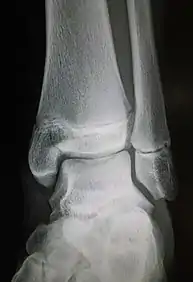

| Radiograph showing a Maisonneuve fracture of the proximal fibula | |